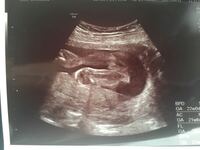

Aug 02, 11 · 妊娠 22週目のエコー写真です、性別が気になります。 22週目の時に頂いたエコー写真です。 先生からは「女の子かな」と言われましたが、その"かな"が気になってしまいます。 ご経験のある方、写真を 質問Noエコーのことで質問なのですが、6ヶ月まで男の子。 4Dでも男の子のシンボルが大きく見えてました! なのに7ヶ月の26週になって先生から「あれ? 前性別言ったかな? 」と言われ「男の子って言ってましたよー」というと 「おちんちんないねー。 女の子かもねー。 」と言われました。 確かにおちんちんにしては大きくない?Rainyさんの妊娠22週目のエコー写真 性別を教えてもらいました 緊急帝王切開で誕生。エコー写真で綴る息子と過ごした252日 エコー写真はこちらを向いた"がい骨"のようでした。まだ脂肪が付いて

Apr 30, 17 · しかし性別を判別できるのは、早くても妊娠5ヶ月に当たる16週頃からとされています。 一般的には~22週頃に性別が分かる というケースが多い様ですが、中には臨月まで分からなかったというケースもあるんですよ。Feb 27, 19 · 22週と比べると、 流石にぷくぷくしています☺️ この時で2 22w2dの頃のエコーです☺︎ 性別は男の子だと判明したエコーです☺︎ ばっちり👌うつってる😳 それに、すごい体勢だわ‼️ 初めてお顔見れて嬉しかったな〜☺️ そしてこちらは、切迫早産Aug 02, 11 · 22週目の時に頂いたエコー写真です。先生からは「女の子かな」と言われましたが、その"かな"が気になってしまいます。ご経験のある方、写真を見てどう思われますか?1ヵ月後の検診まで待てばまた聞けることなのですが、どうしても毎日